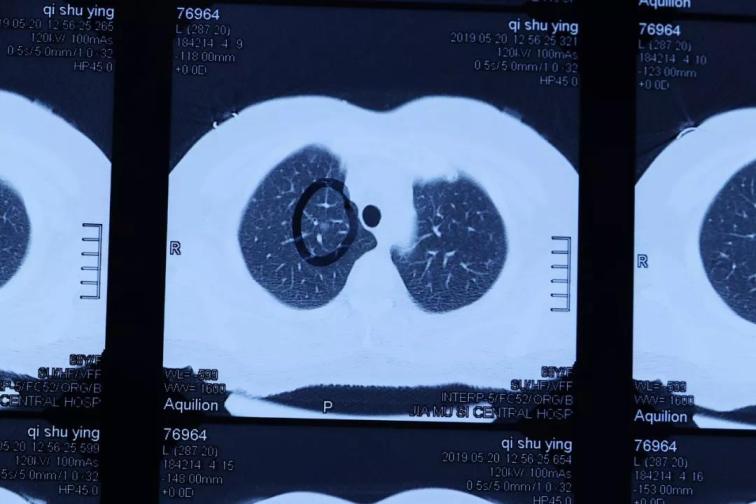

佳木斯大學(xué)宏大醫(yī)院胸心血管外科,在2019年6月收治了一名右肺上葉微小結(jié)節(jié),直徑約4mmX3mm和3X2mm等大小的肺磨玻璃癥。病人女性,63歲,沒有明顯癥狀,在體檢中發(fā)現(xiàn)小結(jié)節(jié)后,前后去過北京協(xié)和醫(yī)院和哈醫(yī)大附屬醫(yī)院就診,沒有明確診斷,進(jìn)行定期復(fù)查處理。來我院就診在心胸外科,經(jīng)過入院后常規(guī)檢查,胸CT掃描薄層小結(jié)節(jié)分析,疑診右肺上葉多發(fā)微小結(jié)節(jié),有癌變傾向。經(jīng)過術(shù)前準(zhǔn)備,周鋼主任手術(shù)團(tuán)隊(duì),在全麻下行胸腔鏡微創(chuàng)右肺上葉切除術(shù),手術(shù)順利。

目前國內(nèi)外肺小結(jié)節(jié)外科手術(shù)的最小標(biāo)準(zhǔn)在8mm以上,且多為實(shí)性結(jié)節(jié),對(duì)肺小結(jié)節(jié)的手術(shù)定位和病理檢查、臨床診斷是公認(rèn)的技術(shù)難題。佳木斯大學(xué)宏大醫(yī)院胸心血管外科和病理科,通過影像學(xué)檢查對(duì)肺小于5mm微小小結(jié)節(jié)精準(zhǔn)分析,采用連續(xù)超薄病理切片檢查,診斷了肺小結(jié)節(jié)肺磨玻璃癥,病灶直徑僅僅在4mm和3mm以下,達(dá)到了國際先進(jìn)水平,填補(bǔ)了黑龍江省微小超早原位肺癌外科微創(chuàng)治療及病理診斷的空白,為肺癌患者早期診斷、早期治療帶來了福音。CT影像、胸外微創(chuàng)手術(shù)和病理診斷技術(shù)值得推廣,標(biāo)志著佳木斯大學(xué)宏大醫(yī)院胸心血管外科、病理科、影像科具有完成高水準(zhǔn)、高難度的診斷及治療水平。